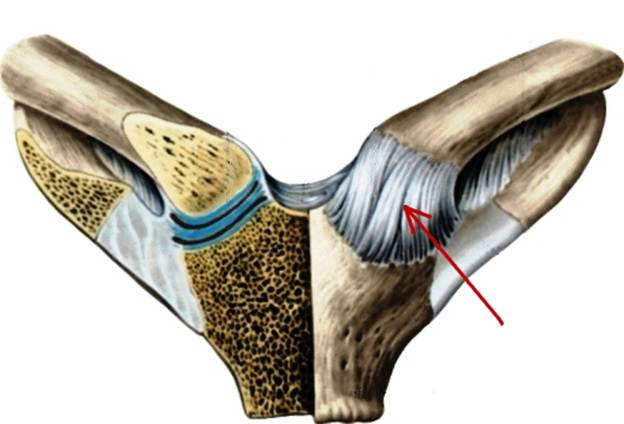

S: Стрелка указывает на art. Costotransversaria

S: Стрелка указывает на art. Capitis costae

S: Стрелками выделен art…